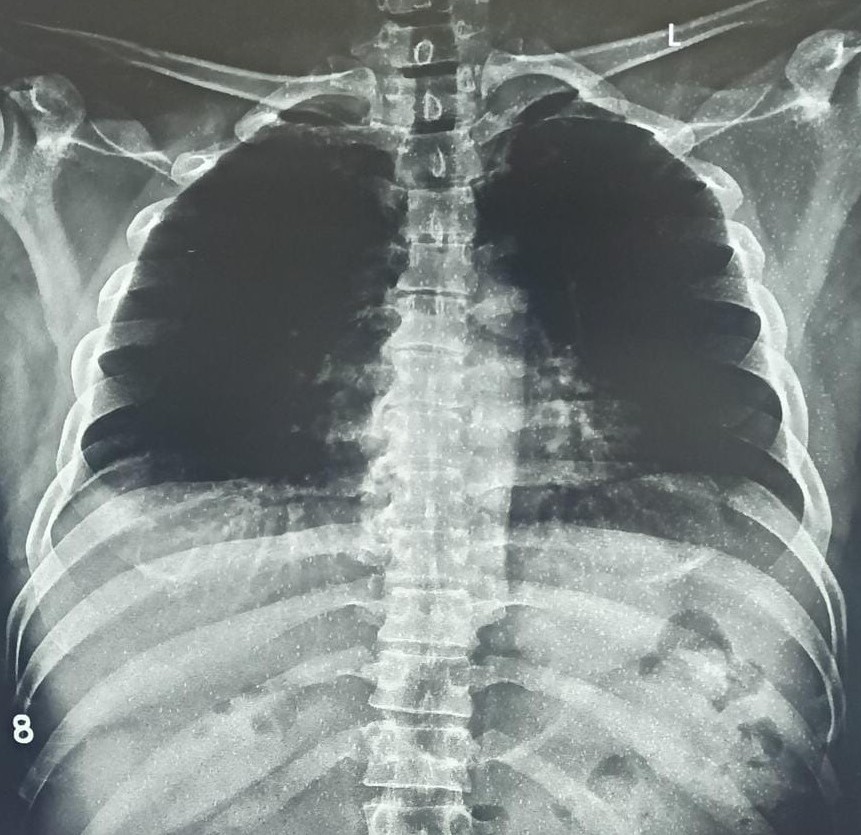

| 4422 | IGGMC, Nagpur, Nagpur | P2 | 29-50 | Vinod Mukardam | Consent taken on Paper | 35 Yrs. |

Provisional Diag : BREATHLESSNESS UNDER EVALUATION

Final Diag : Post TB sequalae (CxR- Bilateral Upper Zone Collapse With Pleural Effusion) |

Post TB Sequelae | Blunting of both lung costophrenic (CP) angles and a trachea shifted towards the right on a chest X-ray | Abnormality visible on x-ray |